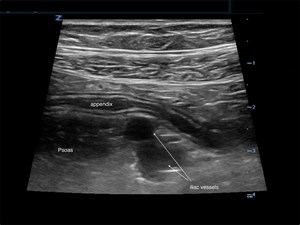

A 55-year-old helmeted male with a past medical history of hypertension, hyperlipidemia, and hypothyroidism, presented with left ankle pain and left leg pain after hitting black ice and falling while ...